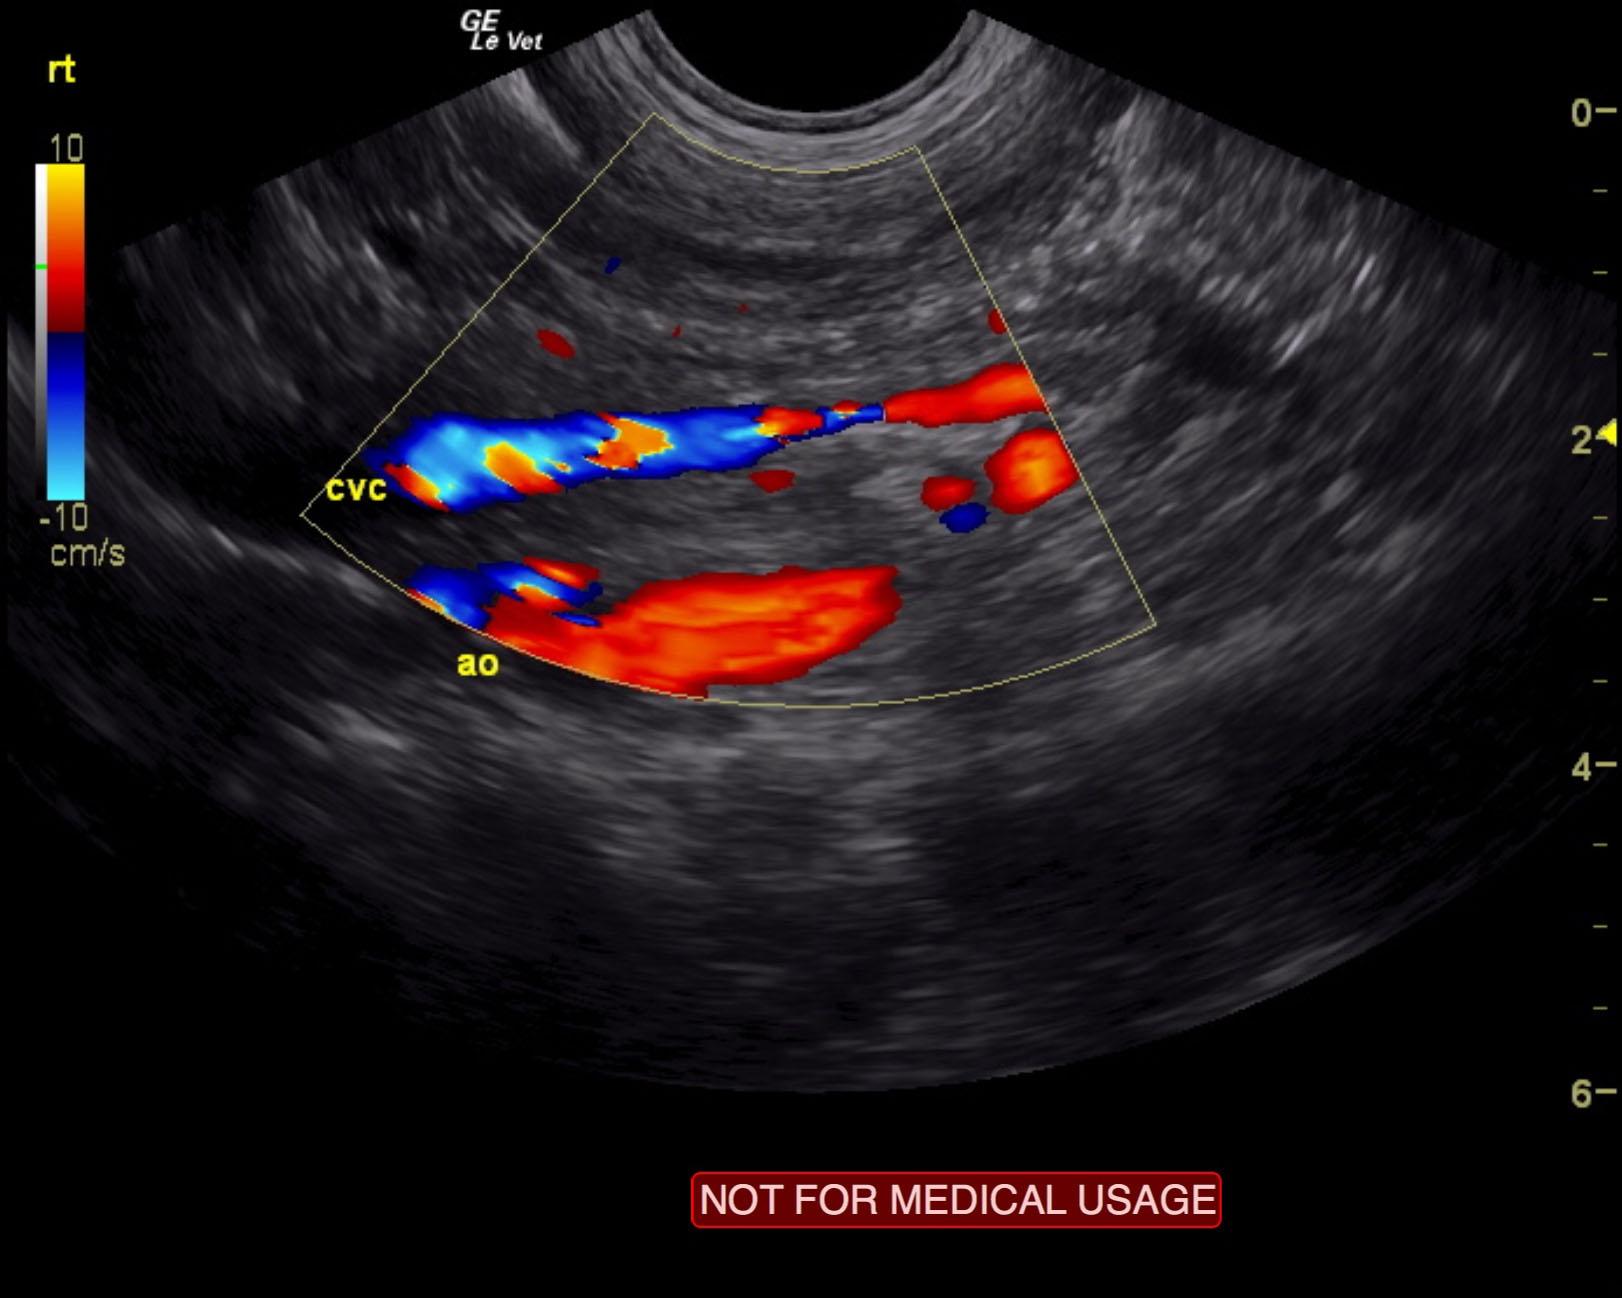

Extrahepatic portosystemic shunt, likely splenoazygos. Microhepatica.

The liver was significantly subnormal in size at 2.1 cm in short axis. A splenazygous shunt was noted in this patient and measured 0.85 cm in width and approximately 1.8 cm in length prior to entering dorsally into the vena cava. The pre-shunt portal vein measured 0.5 cm. Vena cava after the shunt measured 0.5 cm, and the aorta was 0.6 cm. Residual portal vein 0.3 cm. It appears that the shunt exits the splenic entry to the portal vein and creates a “double aorta” appearance cranial to the diaphragm, which is most consistent with a splenoazygos shunt. Hepatic parenchyma was hypovascular and relatively uniform with slightly increased portal markings. Concurrent inflammatory hepatopathy is likely along with the extrahepatic portosystemic shunt. The gallbladder was unremarkable.